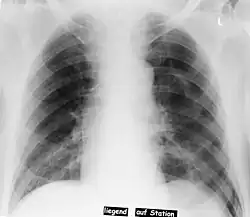

Pneumothorax left sided

In radiology, the deep sulcus sign on a supine chest radiograph is an indirect indicator of a pneumothorax.[1][2] In a supine film, it appears as a deep, lucent, ipsilateral costophrenic angle[3] within the nondependent portions of the pleural space as opposed to the apex (of the lung) when the patient is upright. The costophrenic angle is abnormally deepened when the pleural air collects laterally, producing the deep sulcus sign.[4]

Patients with chronic obstructive pulmonary disease (COPD) may exhibit deepened lateral costophrenic angles due to hyperinflation of the lungs and cause a false deep sulcus sign.[4]